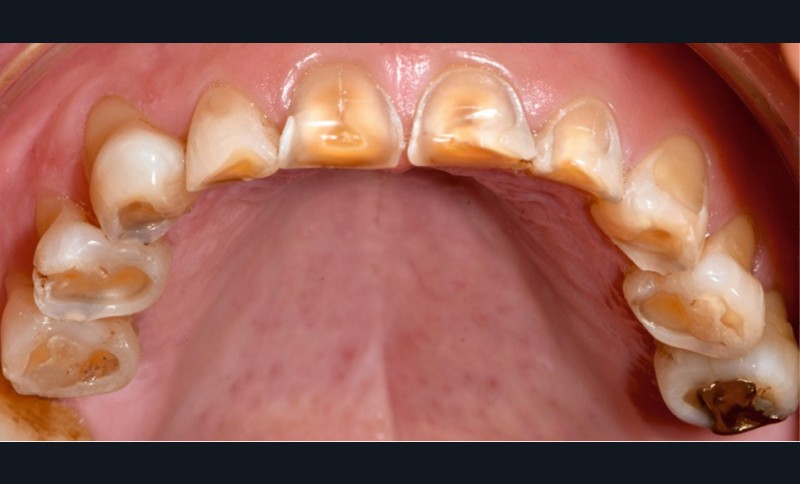

Le cas clinique présenté ici illustre cette démarche thérapeutique. À la suite d’un diagnostic de cancer des voies aérodigestives supérieures, un patient de 68 ans a bénéficié d’un traitement par radiothérapie cervico-faciale, terminée depuis plus de 2 ans. Il souhaite désormais retrouver une réhabilitation fonctionnelle et esthétique de sa cavité orale. Il indique que le délabrement de ses dents antérieures est à l’origine d’un important préjudice esthétique, qui l’a conduit à ne plus sourire. De plus, ses dents absentes réduisent fortement ses capacités masticatoires. Ces différents facteurs influent donc directement son estime de soi et sa qualité de vie, paramètres clés de la rémission dans le cadre oncologique. À l’examen clinique, il présente une perte de calage postérieur, avec des édentements terminaux secteur 2 et 4, ainsi que de volumineuses pertes de substance au niveau des dents présentes (fig. 1).